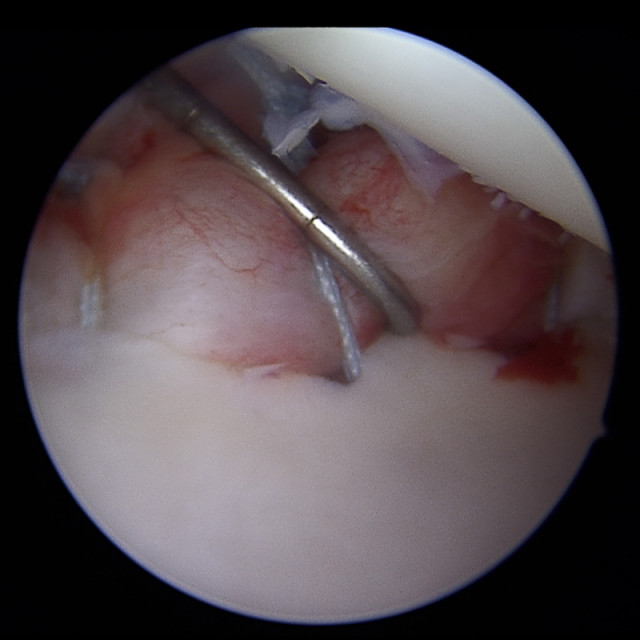

Tasthaken

Mit einem Tasthaken wird die angenähte Kapsel auf ihre Stabilität getestet.